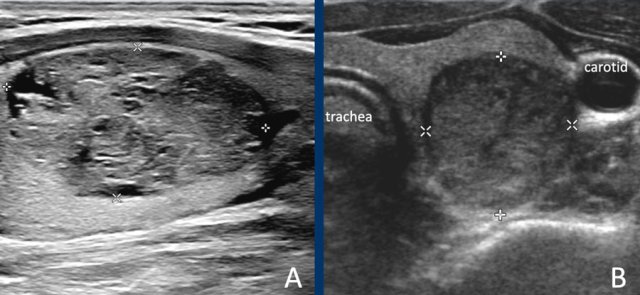

Solid lesions

The lesion in A is almost completely solid.

While there are small cystic parts, it is not considered a spongiform nodule, because the small cystic parts are far less than 50% of the total nodule.

The lesion in B is completely solid.

In solid nodules at least 95% of the nodule should be solid.

This percentage should be an estimation, it is not needed to calculate this.